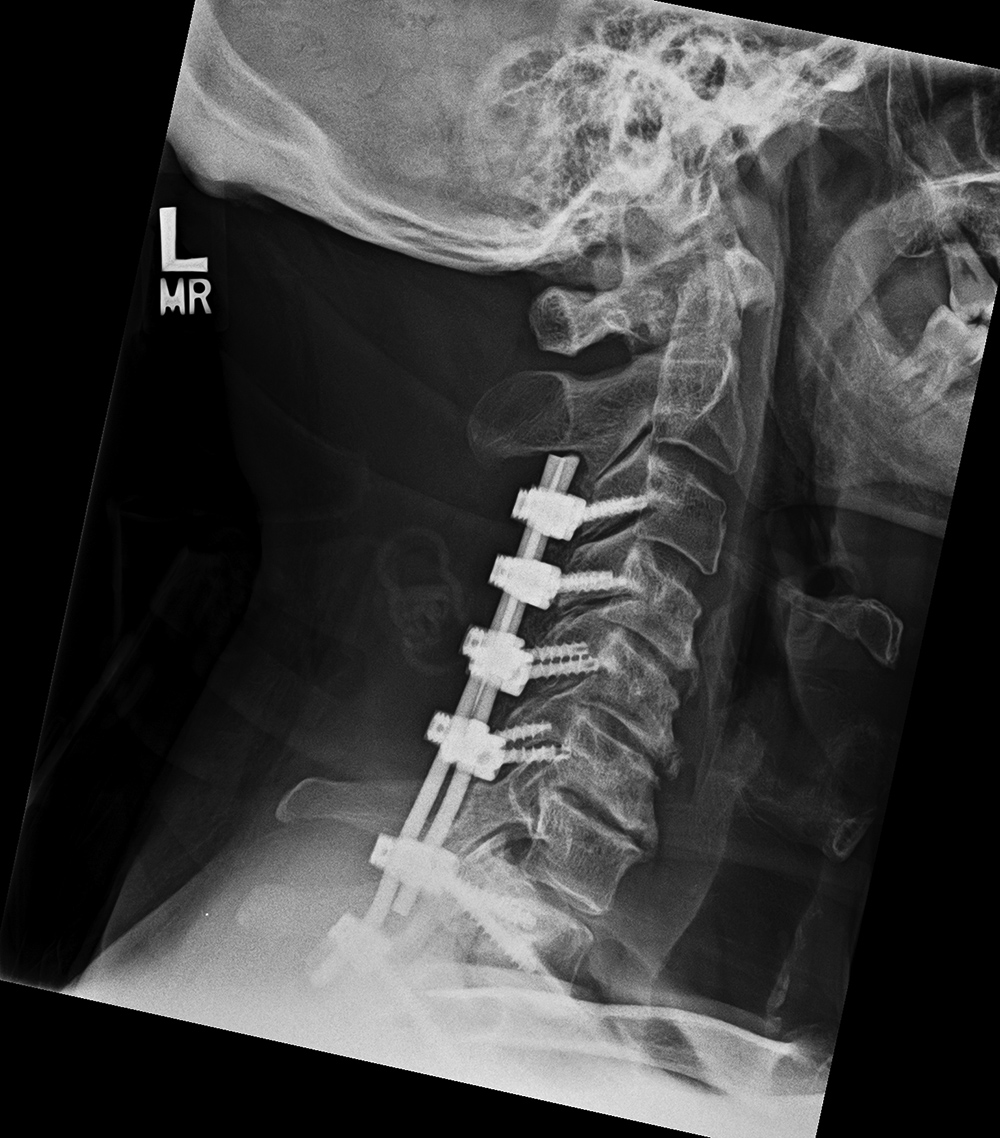

| Posterior cervical spine fusion from occiput with halo brace |

| 53 year-old man with congenital cervical spine fusion and traumatic fracture through fusion mass at C3-7. The spine is stabilized by surgical fusion hardware from the occiput to T2 plus a halo brace. |